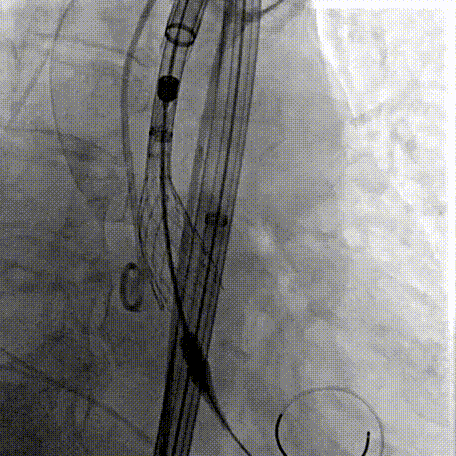

Step 2.建立大鞘通路:大鞘通过升主、边进入边加弯,避免剐蹭弓部斑块

Step 3.球囊预扩:18mm球囊预扩张,无腰无漏

Step 4.输送系统进入:过弓性能优异,悬空通过,整体过程未将鞘管顶起至弓顶部

手术中其实有个关键点,在可调弯鞘过弓的时候,我们特意放慢了速度,一遍进一遍调弯,确保每一步都不触碰弓顶钙化。这台手术的成功,本质上是 “病变特点和器械特性” 的精准匹配。对同类型来说,碰到瓷化升主动脉合并复杂弓的病例,建议术前一定要把钙化范围、弓部角度这些解剖细节分析透,器械选择上不用局限于单一方案,多考虑协同作用,或许能找到更安全的路径。毕竟对我们来说,每台复杂手术的目标都一样:在保证安全的前提下,给患者带来最好的长期获益。